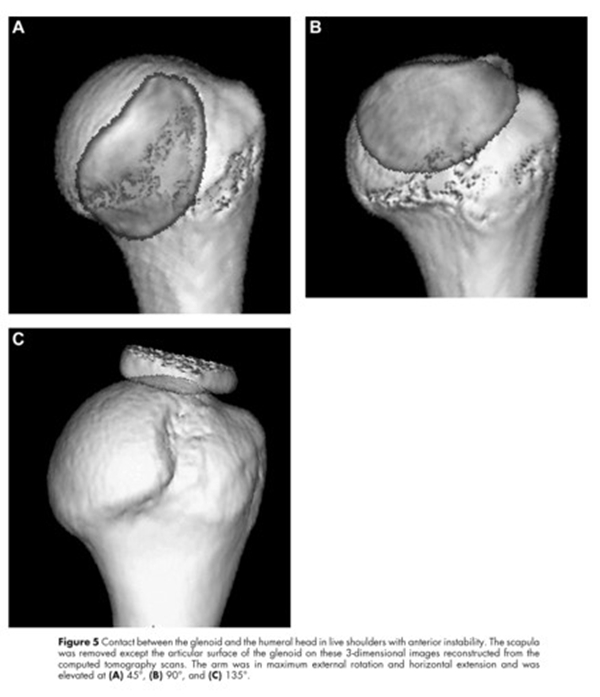

2007年日本仙台东北大学Eiji Itoi教授和Nobuyuki Yamamoto提出肩关节盂肱运动轨迹的概念。

图10

当手臂上举时,肩胛盂与肱骨头的接触区域会从肱骨头的中下部向外上部分转移,这个相互的接触区域就被称为肩胛盂轨迹。接触区域的内侧缘到肩袖止点的内侧缘的距离约为84%肩胛盂的宽度。

图12

当没有肩胛盂骨缺损时,肩胛盂轨迹的宽度占了肩胛盂宽度的84%。当有肩胛盂前缘骨缺损时,应该从这84%的长度中减去骨缺损的宽度,这样才能够获得一个真正的肩胛盂轨迹的宽度。

2014年Giovanni Di Giacomo提出轨迹内/轨迹外损伤,并以此提出分类及治疗策略。

图14

上图显示接触区域的内侧缘到肩袖止点的内侧缘的距离约为83%肩胛盂的宽度。A1-B1是肩胛盂的长轴,C-D是肩胛盂的宽度,E-D是肩胛盂轨迹,为83%肩胛盂的宽度。B图为盂肱关节在外展外旋位的对合关系,肱骨头和肩胛盂接触区域内侧边缘(M)到肩袖足印区的内侧边缘(F)的距离,是肩胛盂宽度的83%±14%。(肩胛盂轨迹=F-M=83%肩胛盂的宽度)。